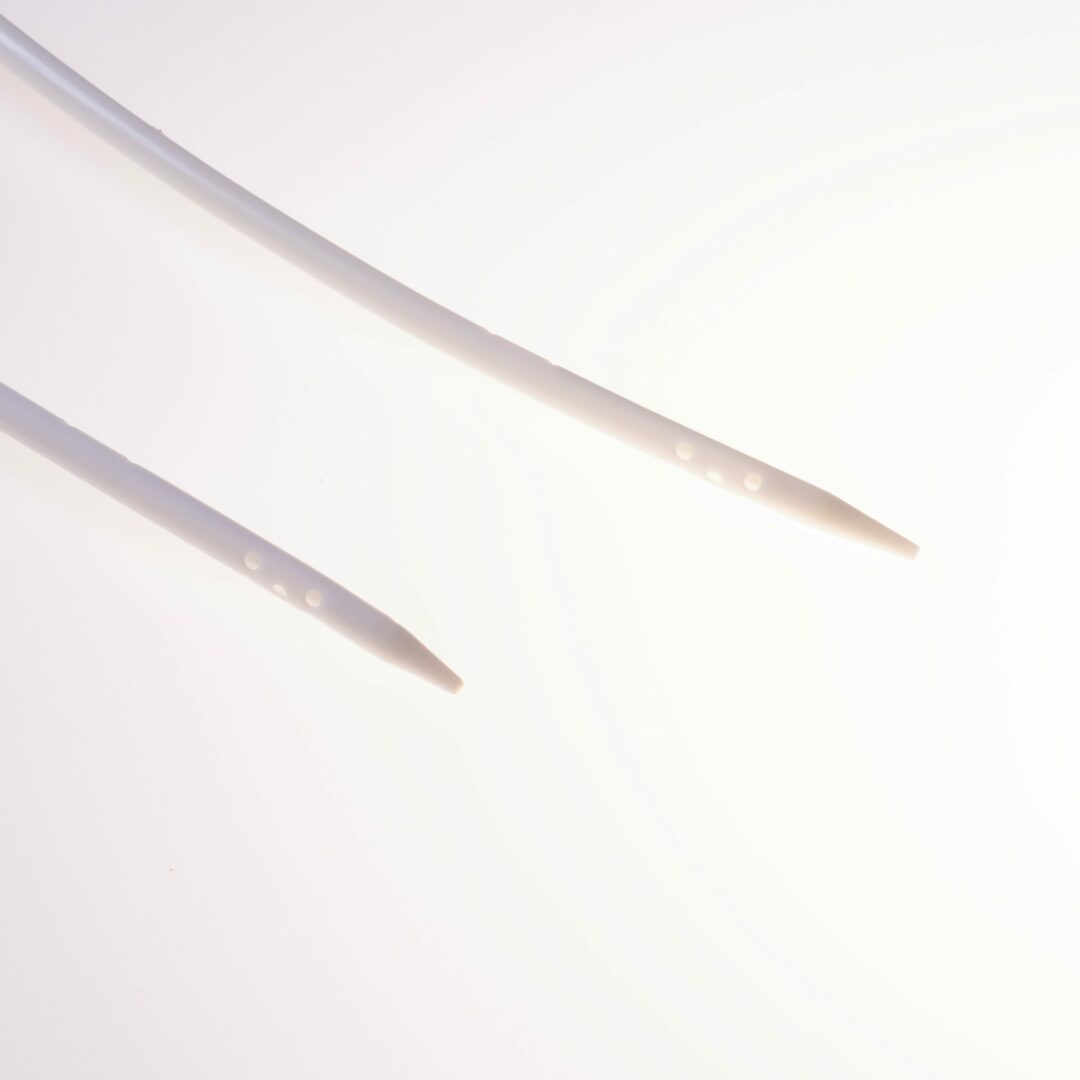

Die Katheterspitze ist gestuft ( tapered ) mit einem Abstand von 3 cm zwischen dem arteriellen und venösen Schenkel.